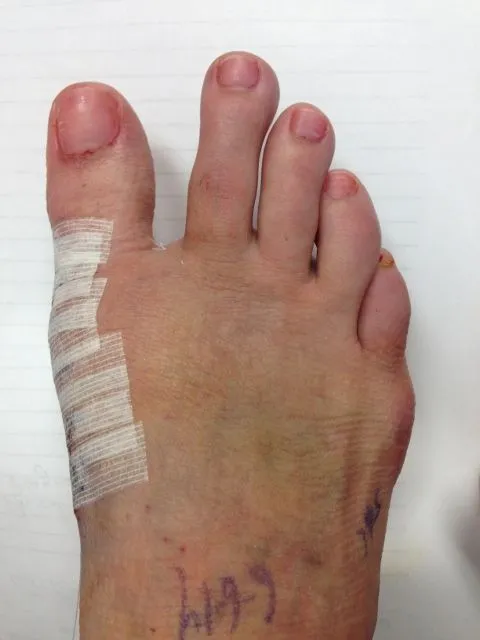

Pre and Postop Bunionectomy

Pre and Post op Pictures and X-rays Bunionectomy with 1st metatarsal osteotomy